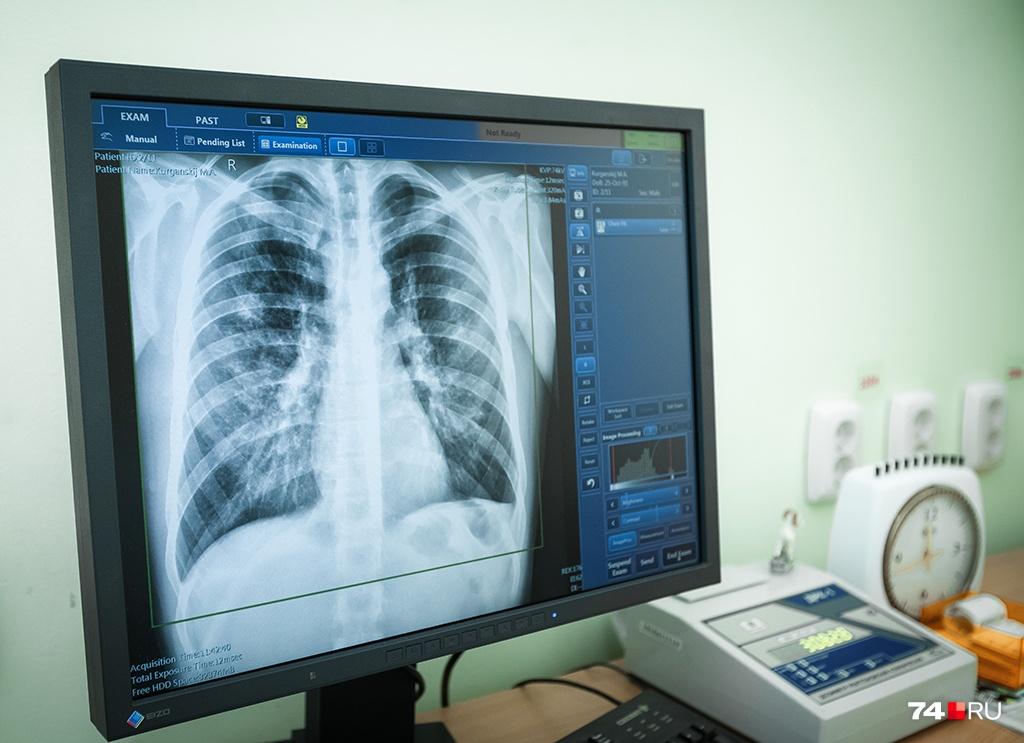

Начальник Братского филиала ОГБУЗ ИОКТБ Сергей Нехороших принял участие в работе круглого стола для руководителей центров реабилитации. Говорили о распространении заболевания в Братске, в частности, подняли проблему проведения флюорографического исследования лицам без определенного места жительства.